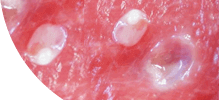

ГЕЛЬМИНТЫ ПОРАЖАЮТ ИЗНУТРИ, РАЗМНОЖАЮТСЯ И ВЫЗЫВАЮТ СМЕРТЕЛЬНЫЕ ЗАБОЛЕВАНИЯ!

ПОПУЛЯЦИЯ +200,000

Самки паразитов откладывают до 240 000 яиц в кишечнике человека ежедневно.

Размеры гельминтов (глистов) колеблются от нескольких сантиметров до 7-10 метров.